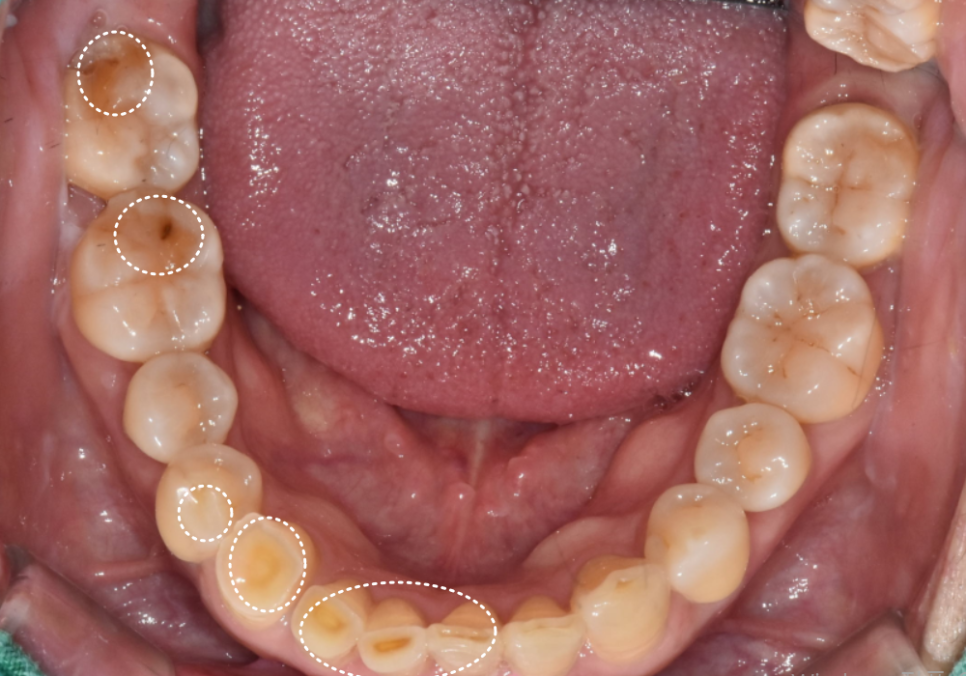

입안을 자세히 살펴보니

원인은 크게 세 가지였습니다.

유독 길게 제작된 위 앞니가

아랫니를 계속 건드리면서,

아랫니 속살(상아질)이 비칠 만큼

심하게 마모되어 있었습니다.

무엇보다 "씹을 때 욱신거린다"는

통증을 호소하셨는데,

정밀 검사 결과 ,

과거 신경치료가 제대로 마무리되지 않아

내부에 염증이 생겨 있었습니다.

230215

결국 기존 재료를 모두 제거하고

다시 치료하는 '재신경치료'가

시급한 상황이었습니다.

아랫니가 이미 많이 닳아

낮아진 상태라,

위 앞니 배열을 반듯하게 맞추면

특정 부위가 아랫니와 맞물리지 않고

살짝 뜨게 되는 구조였거든요.